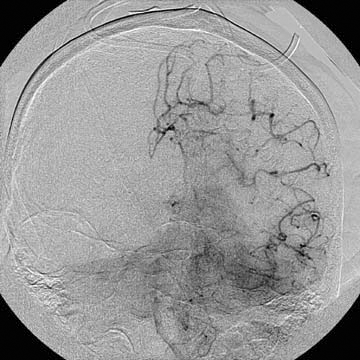

A diagnostic angiography was done during his hospitalization and yielded the following images.